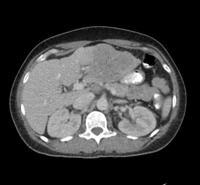

Figure 3. CT abdomen

CT Abdomen showing air showing free air in the peritoneum.